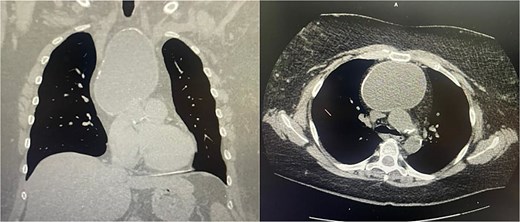

A 51-year-old woman with a history of insulin-dependent type 2 diabetes mellitus and Henoch-Schönlein purpura without history of tobacco or alcohol use presented to the emergency department after being struck by a slow-moving motor vehicle as a pedestrian. On initial evaluation, the patient reported mild shoulder pain but denied any further injuries or symptoms. Workup included a chest X-ray, which demonstrated mediastinal widening suggestive of thoracic aortic ectasia. Non-contrast computed tomography (CT) of the chest revealed a large fluid density in the anterior mediastinum with rim calcification, subtle septations, and some nodularity, measuring 7.1 × 9.2 × 11.2 cm, accompanied by multiple small bilateral pulmonary nodules (Fig. 1). The radiologist was concerned about a possible cystic teratoma. A subsequent positron emission tomography (PET-CT) scan confirmed a photopenic mass in the anterior mediastinum measuring 7.0 × 9.4 cm, with no evidence of regional lymphadenopathy (Fig. 2). The patient remained asymptomatic and elected to undergo surgical resection.

Coronal and axial views of a non-contrast CT of the chest demonstrating a large fluid density in the anterior mediastinum with rim calcification, subtle septations, and some nodularity, measuring 7.1 × 9.2 × 11.2 cm, accompanied by multiple small bilateral pulmonary nodules.